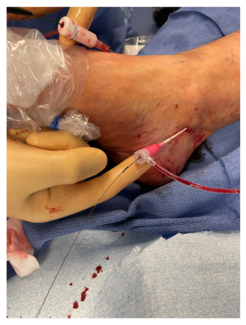

Jetty Ipema, MD, PhD; Alexander C.J. de la Mar, MD; Merel J.C. Betman, MD; Olaf J. Bakker, MD, PhD; Rutger H.A. Welling, MD; Marco G. Manzi, MD; Luis Mariano Palena, MD; Daniel A.F. van den Heuvel, MD

The aim of this study was to present results of ultrasound assisted Angio-Seal VIP closure of antegrade access after peripheral arterial procedures. In addition, the technique of closure is illustrated.